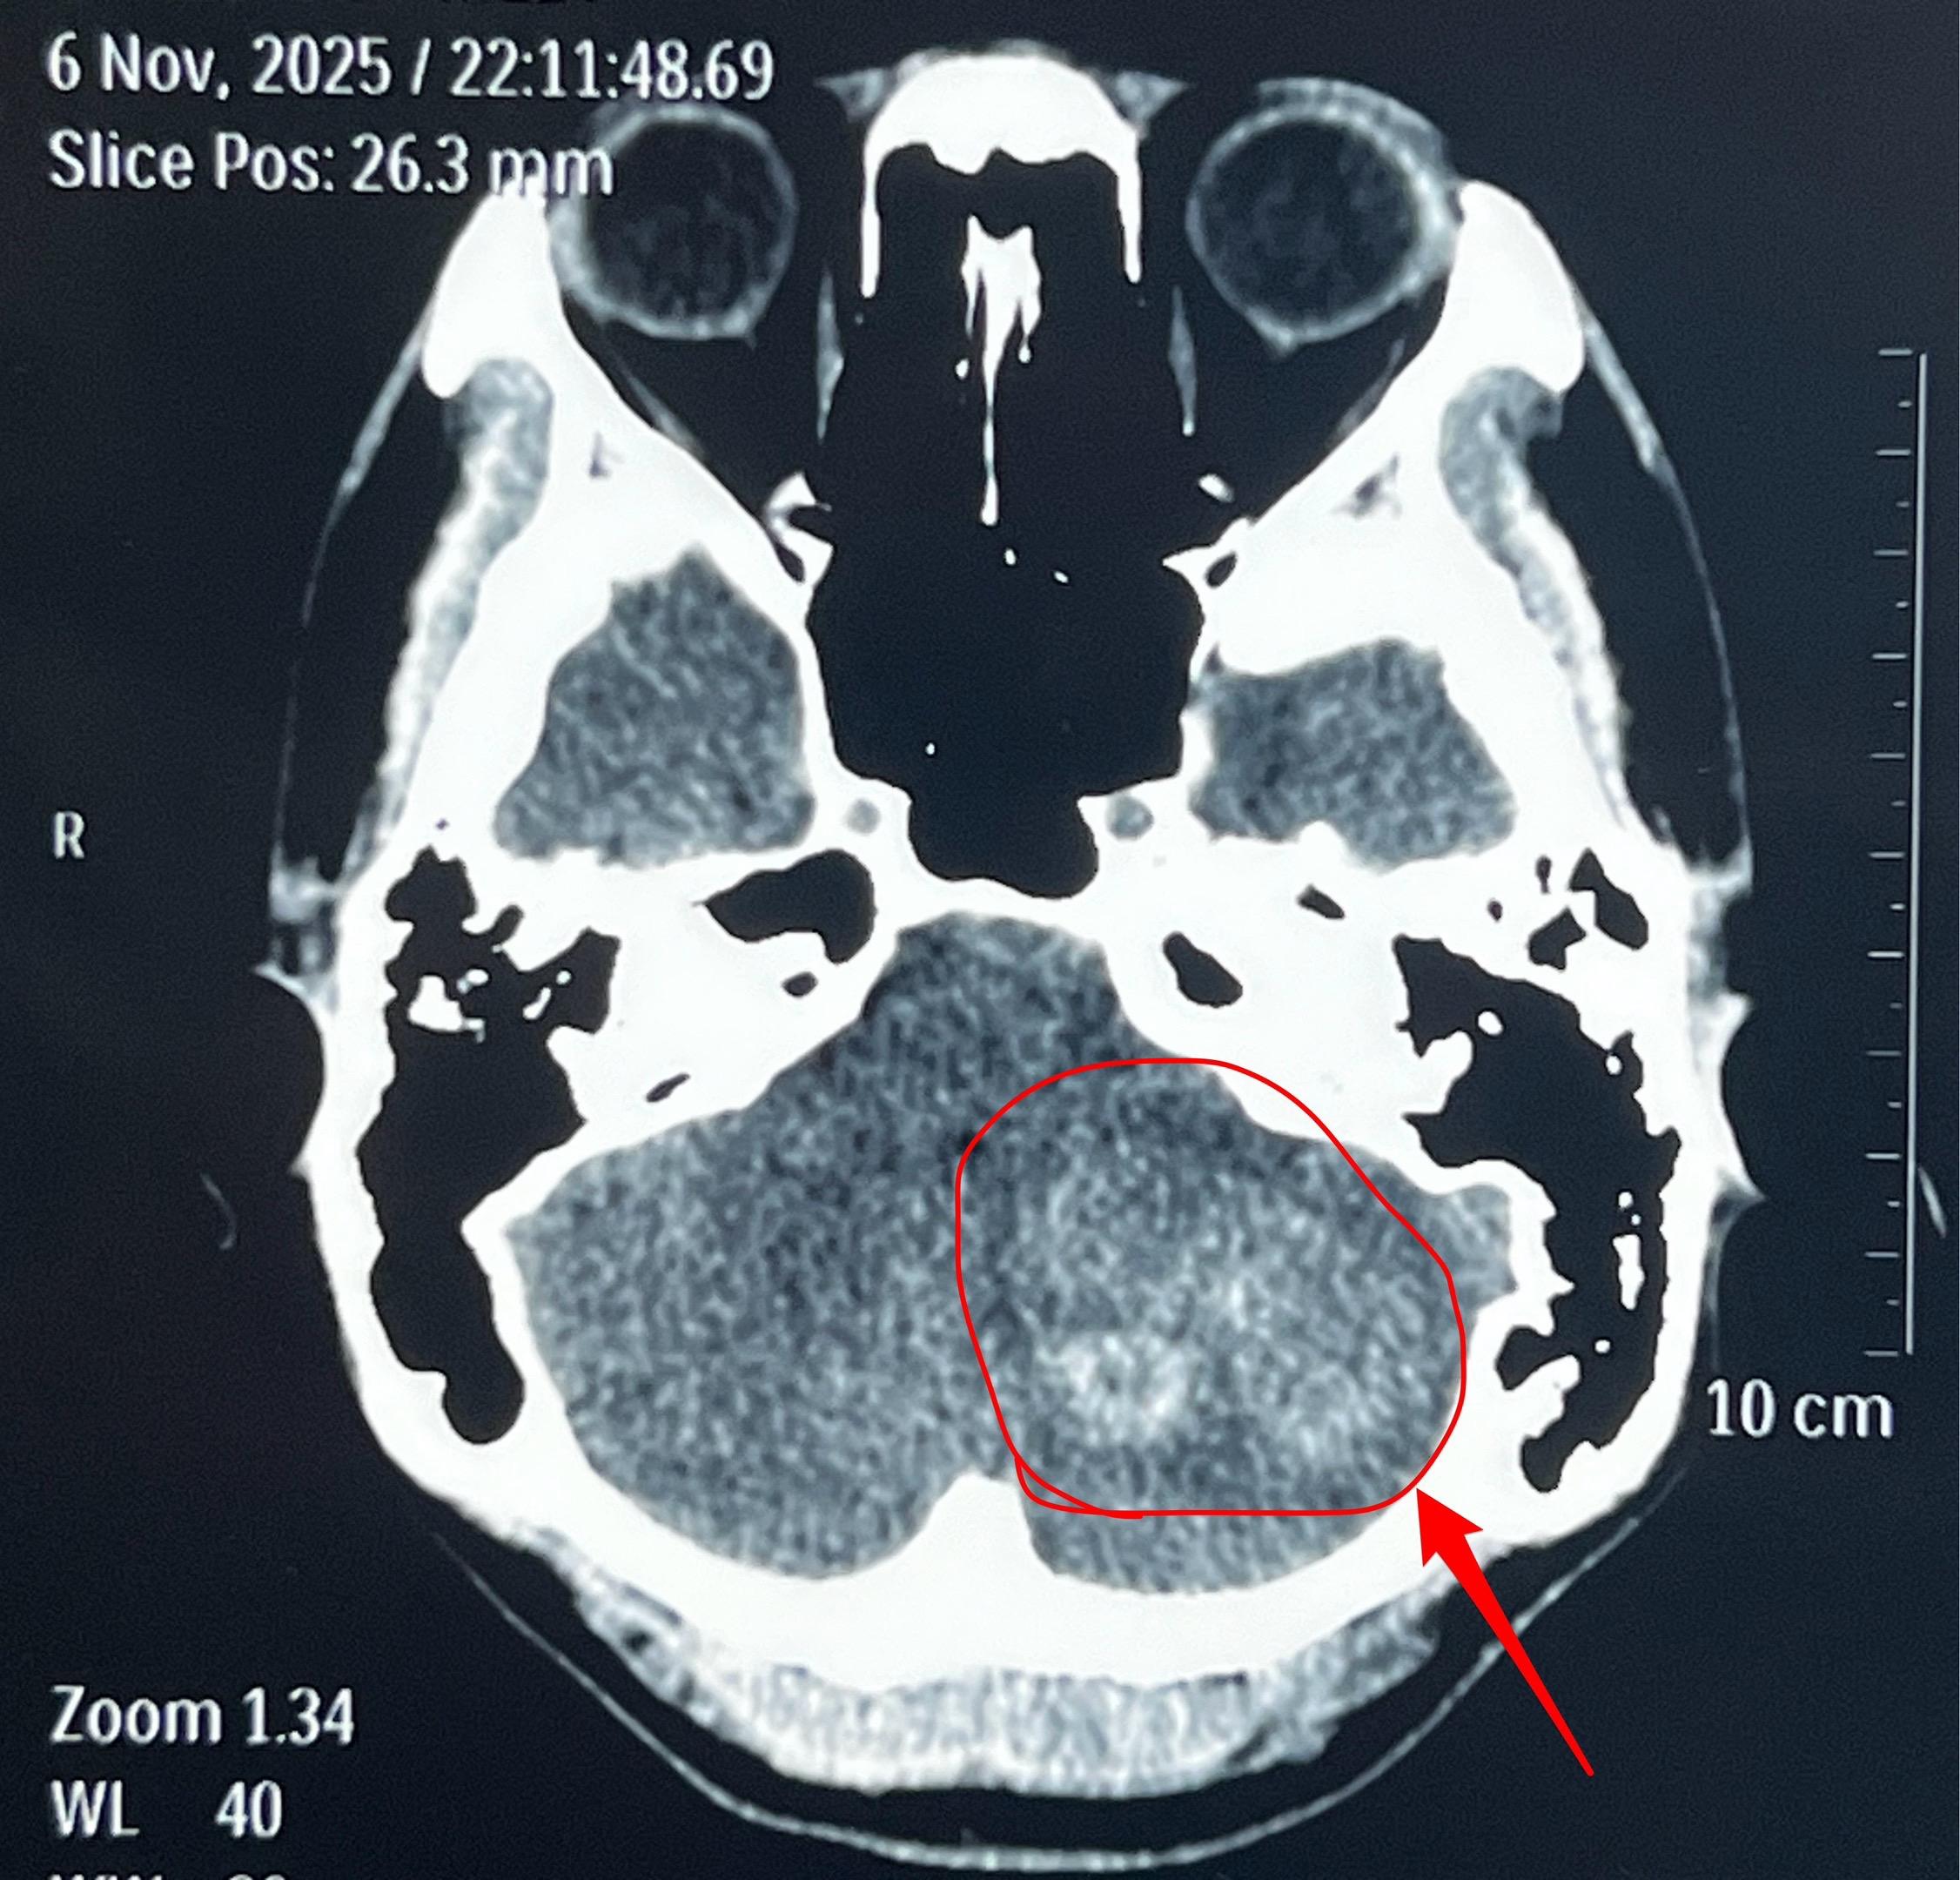

海绵状血管瘤出血。22岁辽宁省小伙子一周前突发头痛、乏力,一周之内几乎是昏昏沉沉、卧床不起。 CT和磁共振显示左侧小脑有陈旧出血。 11月16日作了手术,将病灶完全切除。术中显示病灶是海绵状血管瘤出血。 脑部海绵状血管瘤是先天性血管畸形的一种。如果出血了可能会造成头痛、癫痫发作、偏瘫等症状,需要作手术切除。如果不出血则对病人不造成危害,就不用作手术切除。海绵状血管瘤